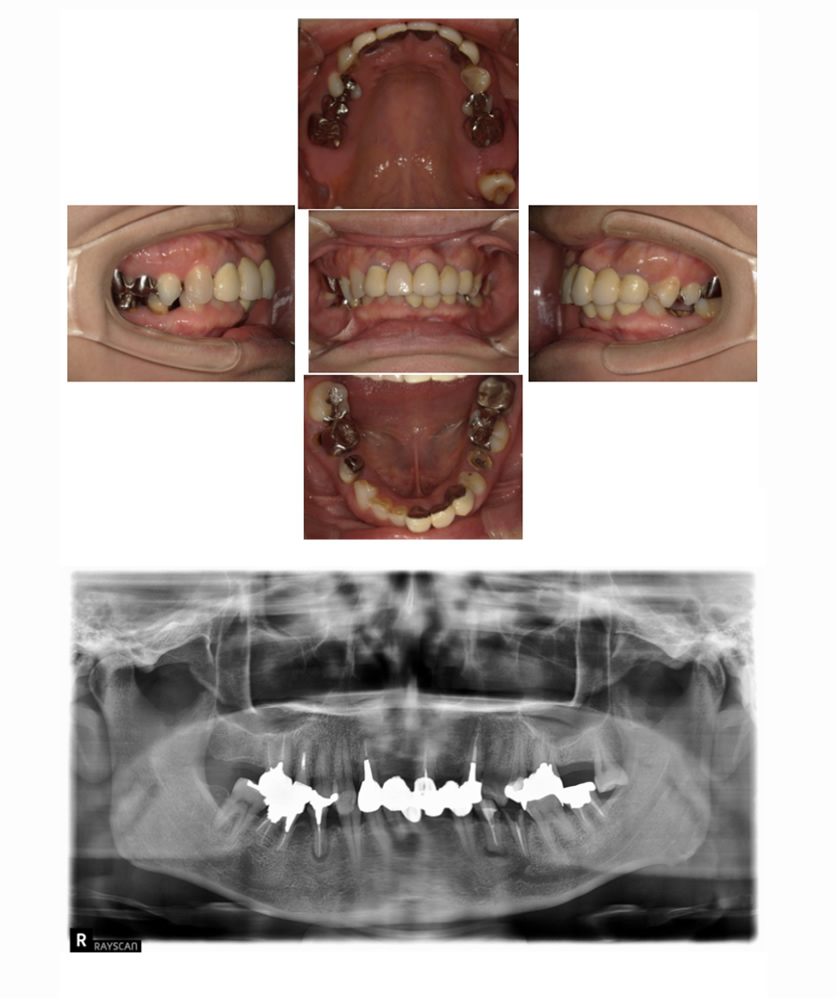

06 症例

歯が割れて痛いのでインプラント希望

Before

After

| 治療内容 | 歯が割れていて咬むと痛いのでインプラント希望 |

| 患者さま | 60代女性 |

| 主訴 | 咬むと痛いのでインプラントにしたい |

| 治療期間(目安) | 3ヶ月 |

| 治療費(税込:目安) | ¥518,100 |

| リスク | 術後に多少の痛みや腫れが出ることがある。歯肉退縮がおきると、歯と歯肉の間に隙間が生じることがあります。 |